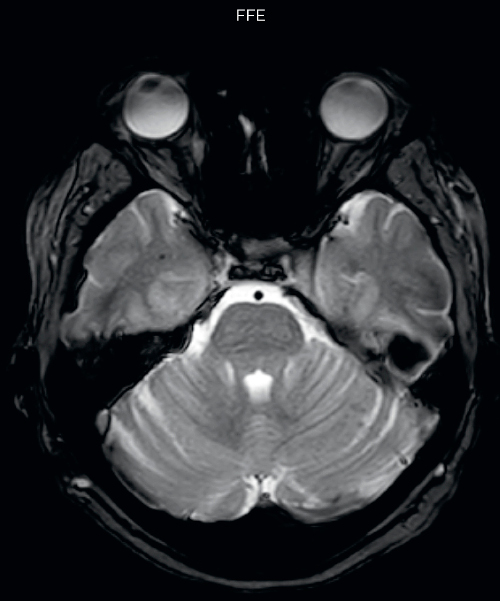

Neuroradiologist Joshua Nickerson, MD, discusses their findings in comparing SWIp versus T2* weighted imaging in different types of patients.

The SWIp sequence offers high resolution 3D susceptibility weighted brain imaging, which helps to visualize deoxygenated blood or calcium deposits. In combination with other clinical information, it may help in the diagnosis of various neurological pathologies

“With SWIp we are basically looking for blood byproducts. It is a sensitive method for visualizing small lesions containing deoxygenated blood. In our comparison, SWIp images are vastly better than gradient echo imaging, there’s no question of that anymore.” “We find the SWIp images very useful in three areas in particular. In patients with a history of hypertension, it offers clear visualization of hemosiderin deposition from hypertensive hemorrhages. We certainly see a greater number of foci of hemosiderin deposition on the SWIp images than on the T2* gradient echo images. In addition, it also helps us visualize amyloid depositions in patients with amyloid angiopathy.” Dr. Nickerson mentions trauma patients are the third large area where SWIp is useful. “We benefit from SWIp in trauma patients, certainly in cases with diffuse axonal injury and shearing injuries. Our study shows that SWIp usually provides us better visualization,” he says. “Apart from these three, SWIp also helps us to beautifully depict the normal venous anatomy in patients with venous outflow issues or vascular congestion. In some cases, we have seen downstream effects of arterial problems. And in patients with vascular malformations we have seen deposition of blood products associated with those.”

“We switched over entirely. SWIp is now included in all our routine brain exams. We developed two different SWIp sequences: a high spatial resolution (0.5 x 0.5 mm) version that takes 5.5 minutes and our fast SWIp that takes just three minutes. Only in patients that are moving tremendously we occasionally still acquire a gradient echo sequence.” “For us, SWIp use has resulted in more diagnostic confidence when small lesions, such as small shear injuries, vascular malformations, or minute amounts of calcification, need to be detected,” says Dr. Nickerson. “Our physicians greatly value the SWIp images. When we get patients transferred from other facilities with SWIp missing from their exam, we have several neurologists and neurosurgeons who order a new MRI exam because they want to see the SWIp images.”

Gradient echo imaging and SWIp are compared in a patient with radiation-induced foci of hemosiderin deposition. A greater number of small foci is seen on the SWIp image. Ingenia 3.0T